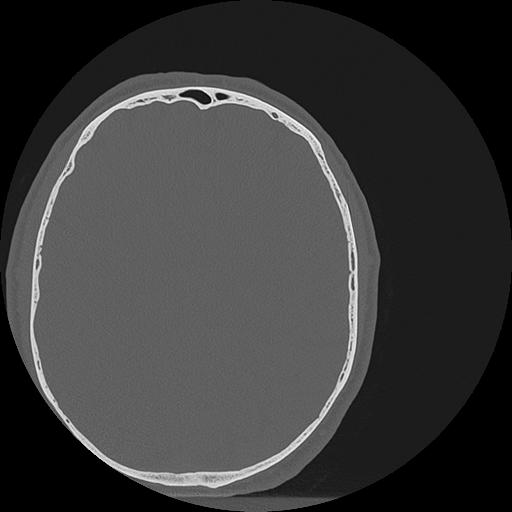

7 HUESO,,Vol,0.5,HUESO,,